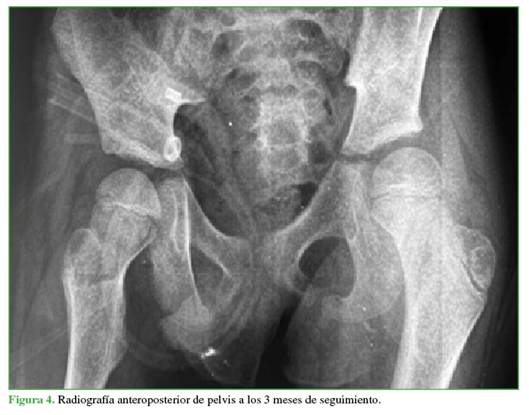

En las radiografías de control a los 3 (Figura 4) y 6 meses (Figura 5), no se visualizaron hallazgos de NAV y también se descartaron otras complicaciones osteomusculares asociadas a la luxación traumática.

Las radiografías de control no mostraron signos sugestivos de NAV (esclerosis, colapso, quistes, reducción del espacio articular, etc.).22 Estos hallazgos pueden demorar de 2 a 6 meses en hacerse visibles en las radiografías,20 por lo que la temporalidad del seguimiento fue adecuada.

A pesar de la ausencia de hallazgos radiológicos de NAV hasta los 6 meses, es necesario continuar con un protocolo de seguimiento con estudios por imágenes en búsqueda de signos de desarrollo de NAV, que pueden demorar hasta 2 años en manifestarse.25